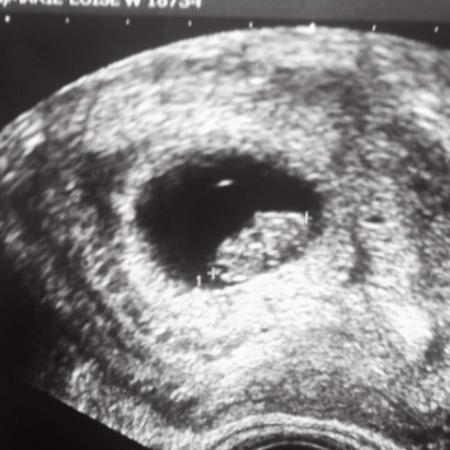

Und das ist in der 11ssw da sieht man dann den unterschied

Bild zu